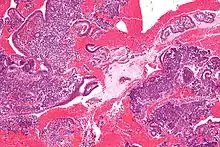

Endometrioid adenocarcinoma from biopsy. H&E stain.